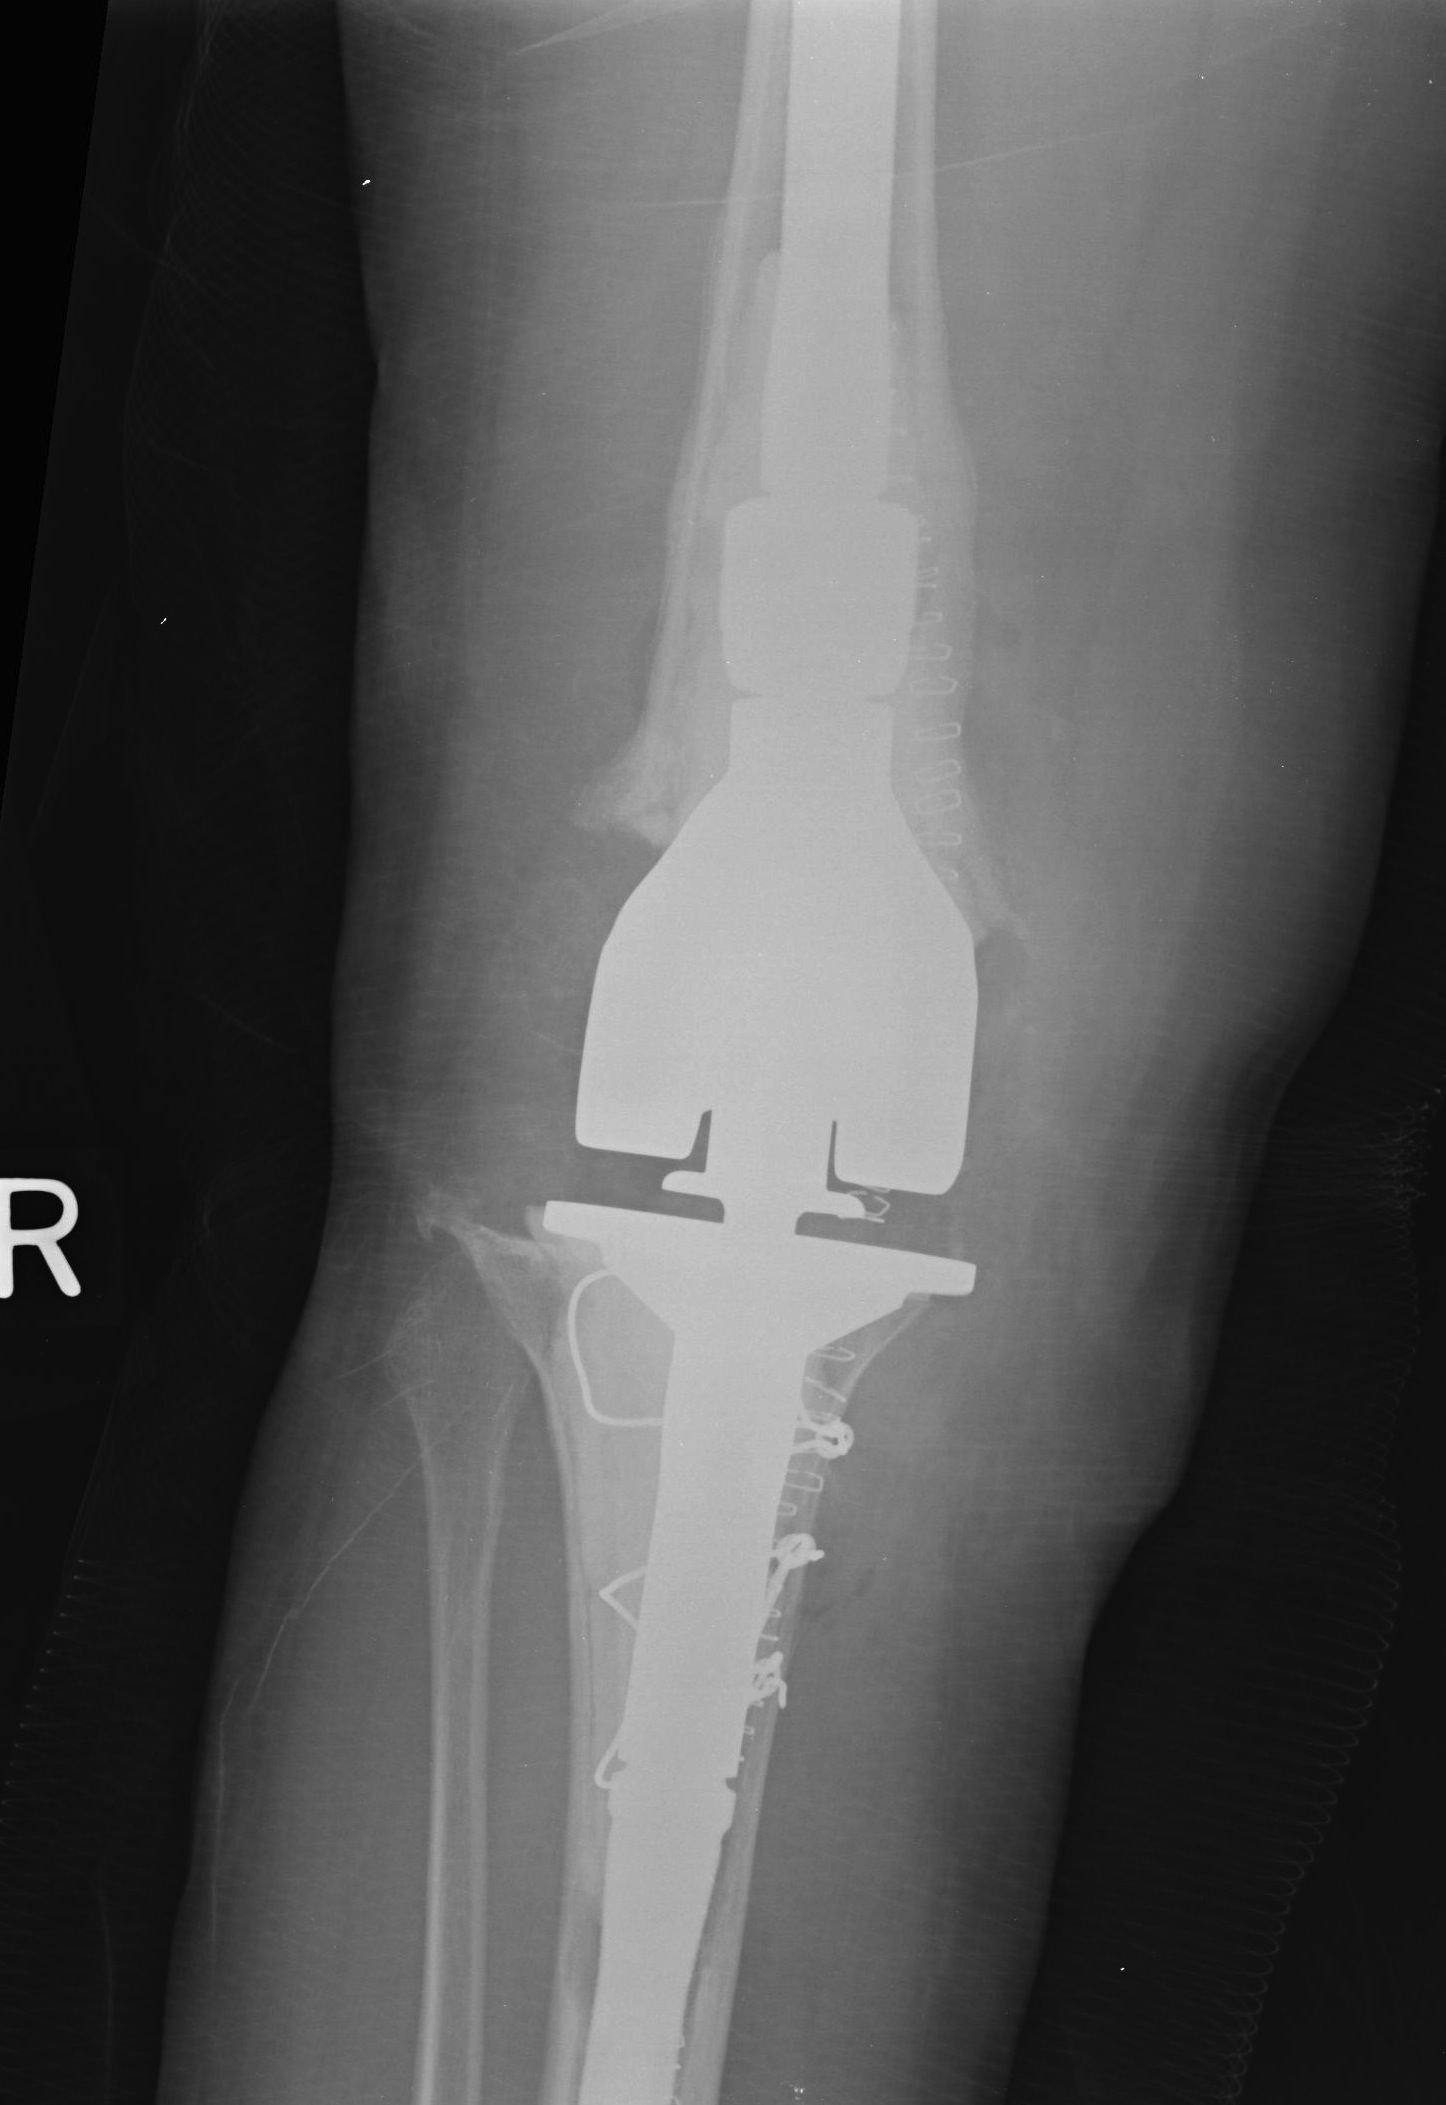

B. Tantalum cones metaphyseal filling / Trabecular metal

C. Mesh + impaction bone grafting

D. Tumour prosthesis / Custom implants